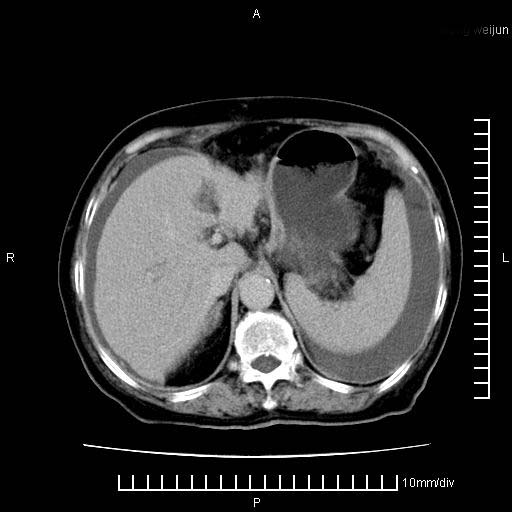

标题: CT28280:腹部增强:女性,80岁

上腹疼痛月余,外院核磁诊断胰腺癌。现临床示右下腹可明显触及包块,可片子上怎么没有看到?

1。胰腺ca伴腹膜腔转移

2。肝左叶低密度灶,考虑转移可能

支持胰腺癌肝内转移,腹水改变。

1、考虑胰腺癌伴腹膜腔转移,胸腹水。

2、肝脏转移可能。

考虑胰腺ca伴腹膜腔转移、肝左叶转移、右肾积水。右胸腔积液。

考虑胰腺ca伴腹膜腔转移、肝左叶转移、右肾积水。右胸腔积液。支持